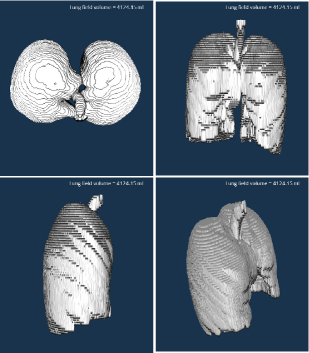

Refer to caption

Figure 4: 3D rendering of the annotation in CIDI-Lung-Seg.